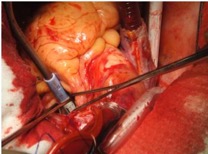

В статье представлен случай успешного хирургического лечения тромбоэмболии легочной артерии у пациентки с высоким риском ранней сердечной смерти на фоне парадоксальной эмболии, осложненной острым нарушением мозгового кровообращения. Криптогенное острое нарушение мозгового кровообращения в комбинации с тяжелой прогрессирующей правожелудочковой недостаточностью на фоне ТЭЛА обусловливает серьезные трудности при принятии решения в отношении тактики лечения у данных больных. Внутрисердечная локализация тромбоэмбола, угрожаемая развитием не только рецидива тромбоэмболии легочной артерии, но и парадоксальной эмболии требует незамедлительного выполнения комплекса дифференциально-диагностического обследования, направленного на верификацию патофизиологического механизма развития заболевания, что во многом определяет эффективность проводимого лечения. Анализ доступных литературных данных, приведенный в работе, а также анализ клинического случая позволяют выработать тактический алгоритм в этой группе пациентов и определить показания к открытому оперативному вмешательству.